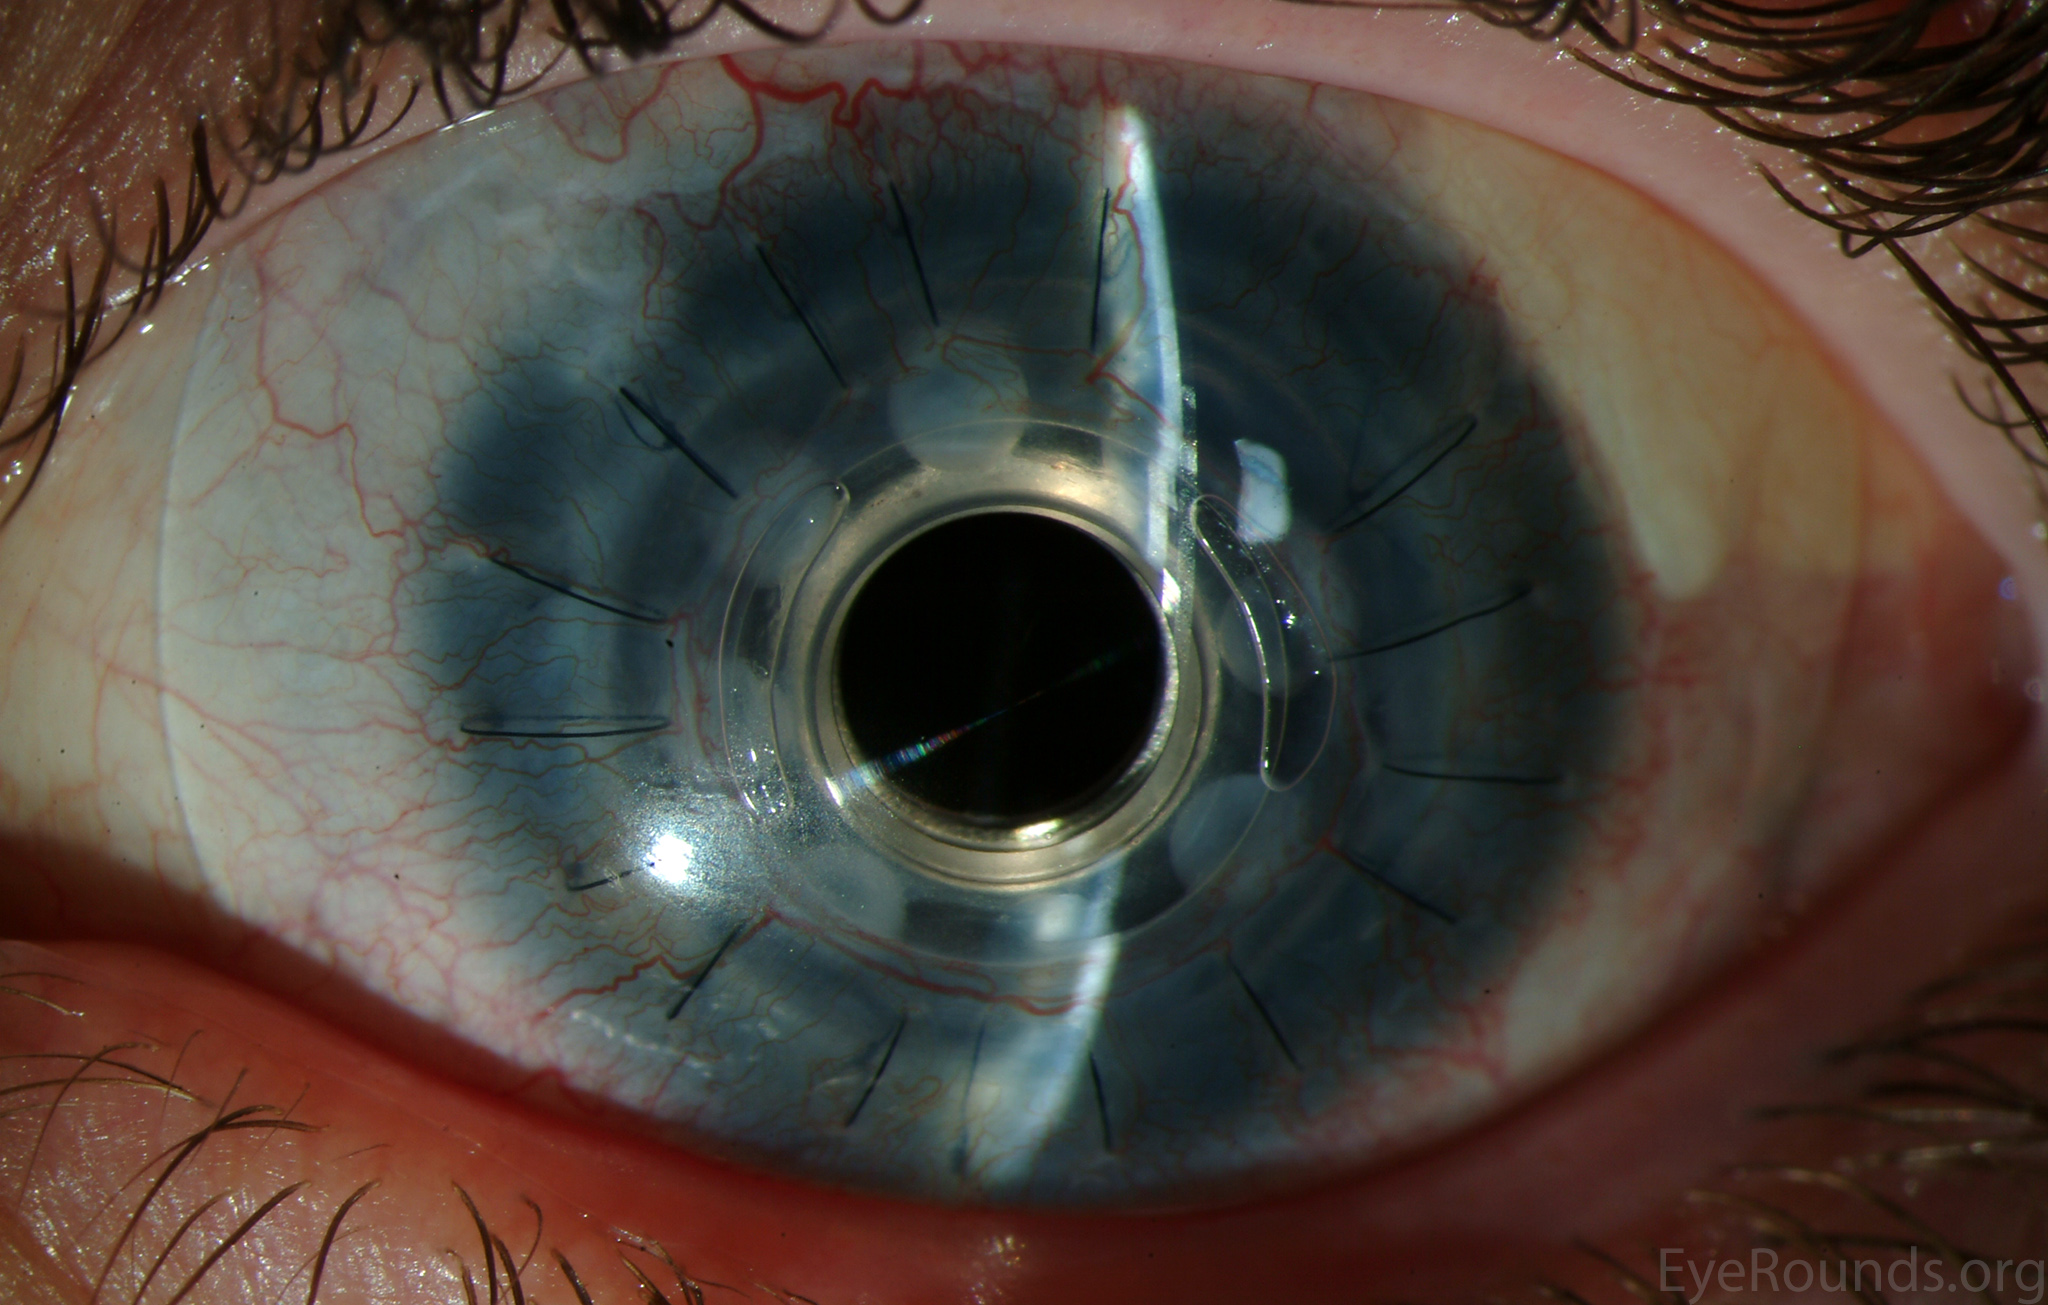

Keratoprosthesis implantation is a procedure that involves full-thickness removal of the cornea and replacement by an artificial cornea. The Boston Type I Keratoprosthesis is currently the most commonly used keratoprosthesis device in the US. It consists of a clear plastic polymethylmethacrylate (PMMA) optic and back plate sandwiched around a corneal graft and secured with a titanium locking ring (Figure 15). After the device is assembled, a partial-thickness trephination is performed on the host cornea. Full-thickness resection of the patient's cornea is then completed using curved corneal scissors. The keratoprosthesis is then secured to host tissue using interrupted or running sutures. Generally, patients who have a history of multiple failed PKs are candidates for a keratoprosthesis transplant. Other indications include severe keratitis or ocular surface disease resulting from limbal stem cell failure, such as Stevens-Johnson syndrome (Figure 16), ocular cicatricial pemphigoid, aniridia (Figure 17) and chemical injury (1, 13). The Boston Type II Keratoprosthesis is a similar device with a longer optic designed to extend through an opening made in the upper eyelid (Figure 19). It is indicated for the most severe cicatrizing ocular surface diseases.